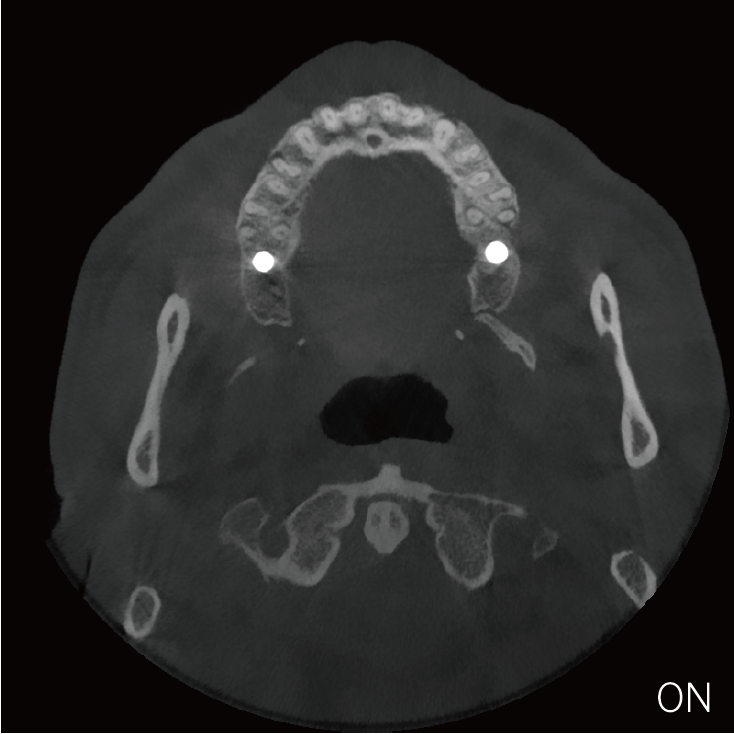

临床样片